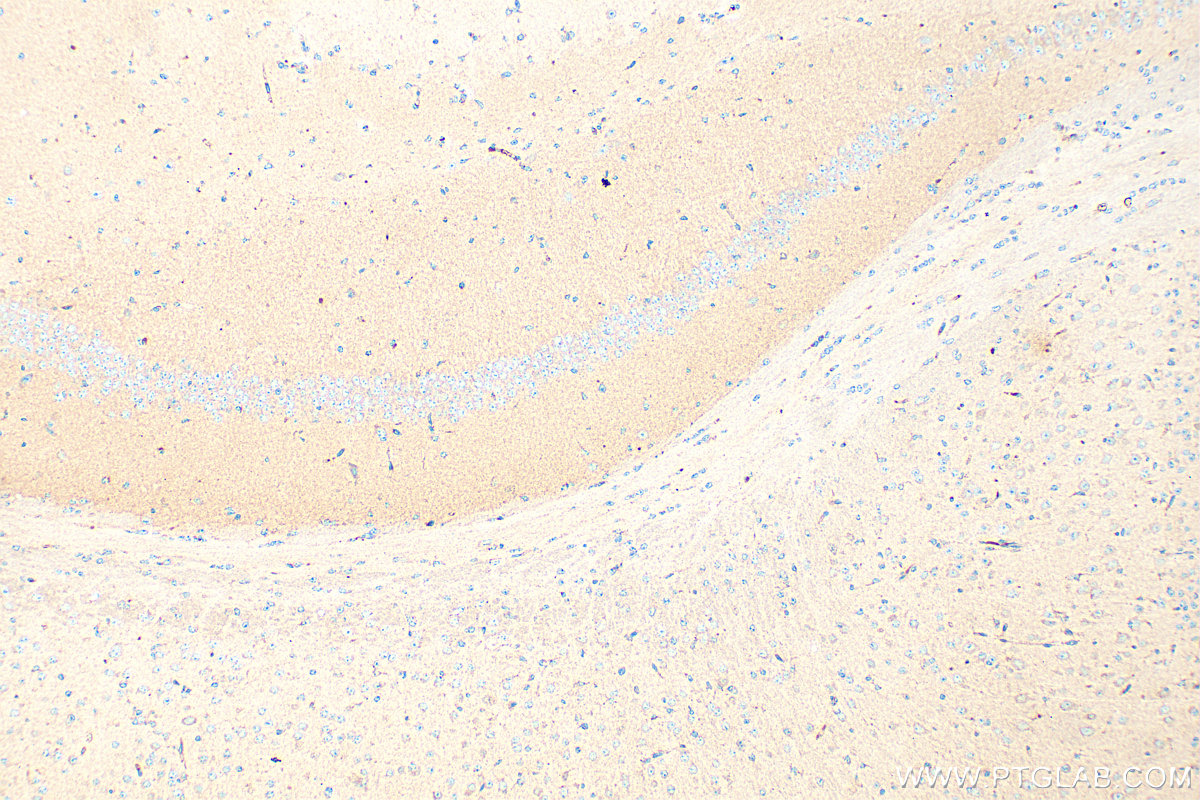

| Positive IHC detected in | mouse brain tissue Note: suggested antigen retrieval with TE buffer pH 9.0; (*) Alternatively, antigen retrieval may be performed with citrate buffer pH 6.0 |

| Immunohistochemistry (IHC) | IHC : 1:200-1:800 |